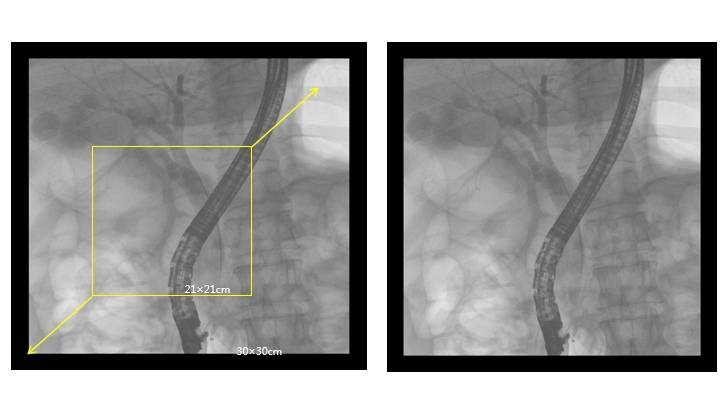

廣闊視野:30cm×30cm的成像面積,能夠一次性全面覆蓋胸、腹、盆腔,減少了多次曝光和輻射的風(fēng)險(xiǎn),同時(shí)避免了檢查中的重疊和遺漏。

大尺寸平板探測(cè)器,成像面積提高一倍以上

高端介入平板C形臂PLX7100A——ERCP臨床圖像:

介入平板C形臂PLX7100A圖像